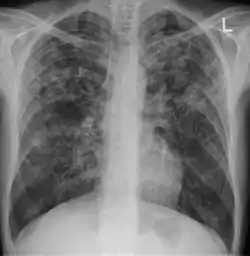

السل الدخني[2] (بالإنجليزية: Miliary tuberculosis) هو شكل من أشكال مرض السل، والذي يتميز بانتشار واسع للآفات ذات الحجم الصغير (1-5 ملم) في جسم الإنسان.

![]() تصوير الصدر بالأشعة السينية يوضح السل الدخني تصوير الصدر بالأشعة السينية يوضح السل الدخني | |